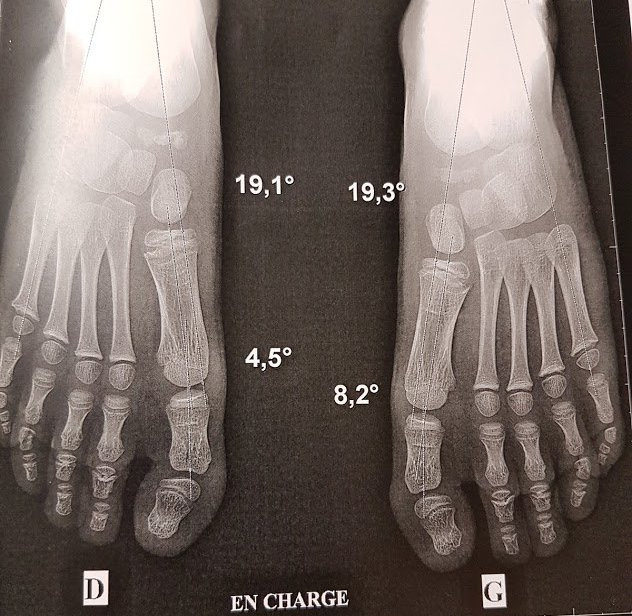

C'est un bilan complet en statique et dynamique du pied (sur tapis de course ou en salle) et de ses interactions avec l’appareil locomoteur.

Apporter votre dossier médical : radio, scanner, IRM, échographie, compte-rendu opératoire...